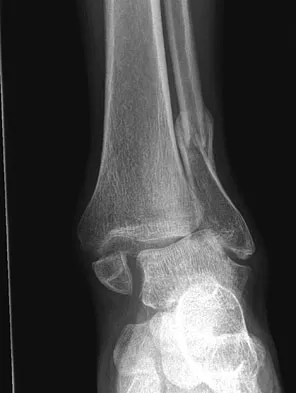

Question 67 High Yield

A 32-year-old laborer reports left ankle pain and deformity. History reveals that he sustained a left ankle fracture 2 years ago and was treated with closed reduction and casting. Radiographs are shown in Figures 25a through 25c. What is the most appropriate management?

Detailed Explanation

Corrective osteotomy of fibular malunions, with appropriate lengthening, even in the presence of early arthritis, has been shown to decrease ankle pain and increase stability. Reduction and bone grafting of the medial malleolar nonunion is also needed. There is no evidence supporting the use of intra-articular steroids or hyaluronic acid in the ankle joint. Lateral talar displacement of even 1 mm has been reproducibly shown to decrease tibiotalar contact by 40% to 42%, causing a predisposition to arthritis. Weber D, Friederich NF, Muller W: Lengthening osteotomy of the fibula for post-traumatic malunion: Indication, technique and results. Int Orthop 1998;22:149-152. Lloyd J, Elsayed S, Hariharan K, et al: Revisiting the concept of talar shift in ankle fractures. Foot Ankle Int 2006;27:793-796. Offierski CM, Graham JD, Hall JH, et al: Later revision of fibular malunion in ankle fractures. Clin Orthop Relat Res 1982;171:145-149.